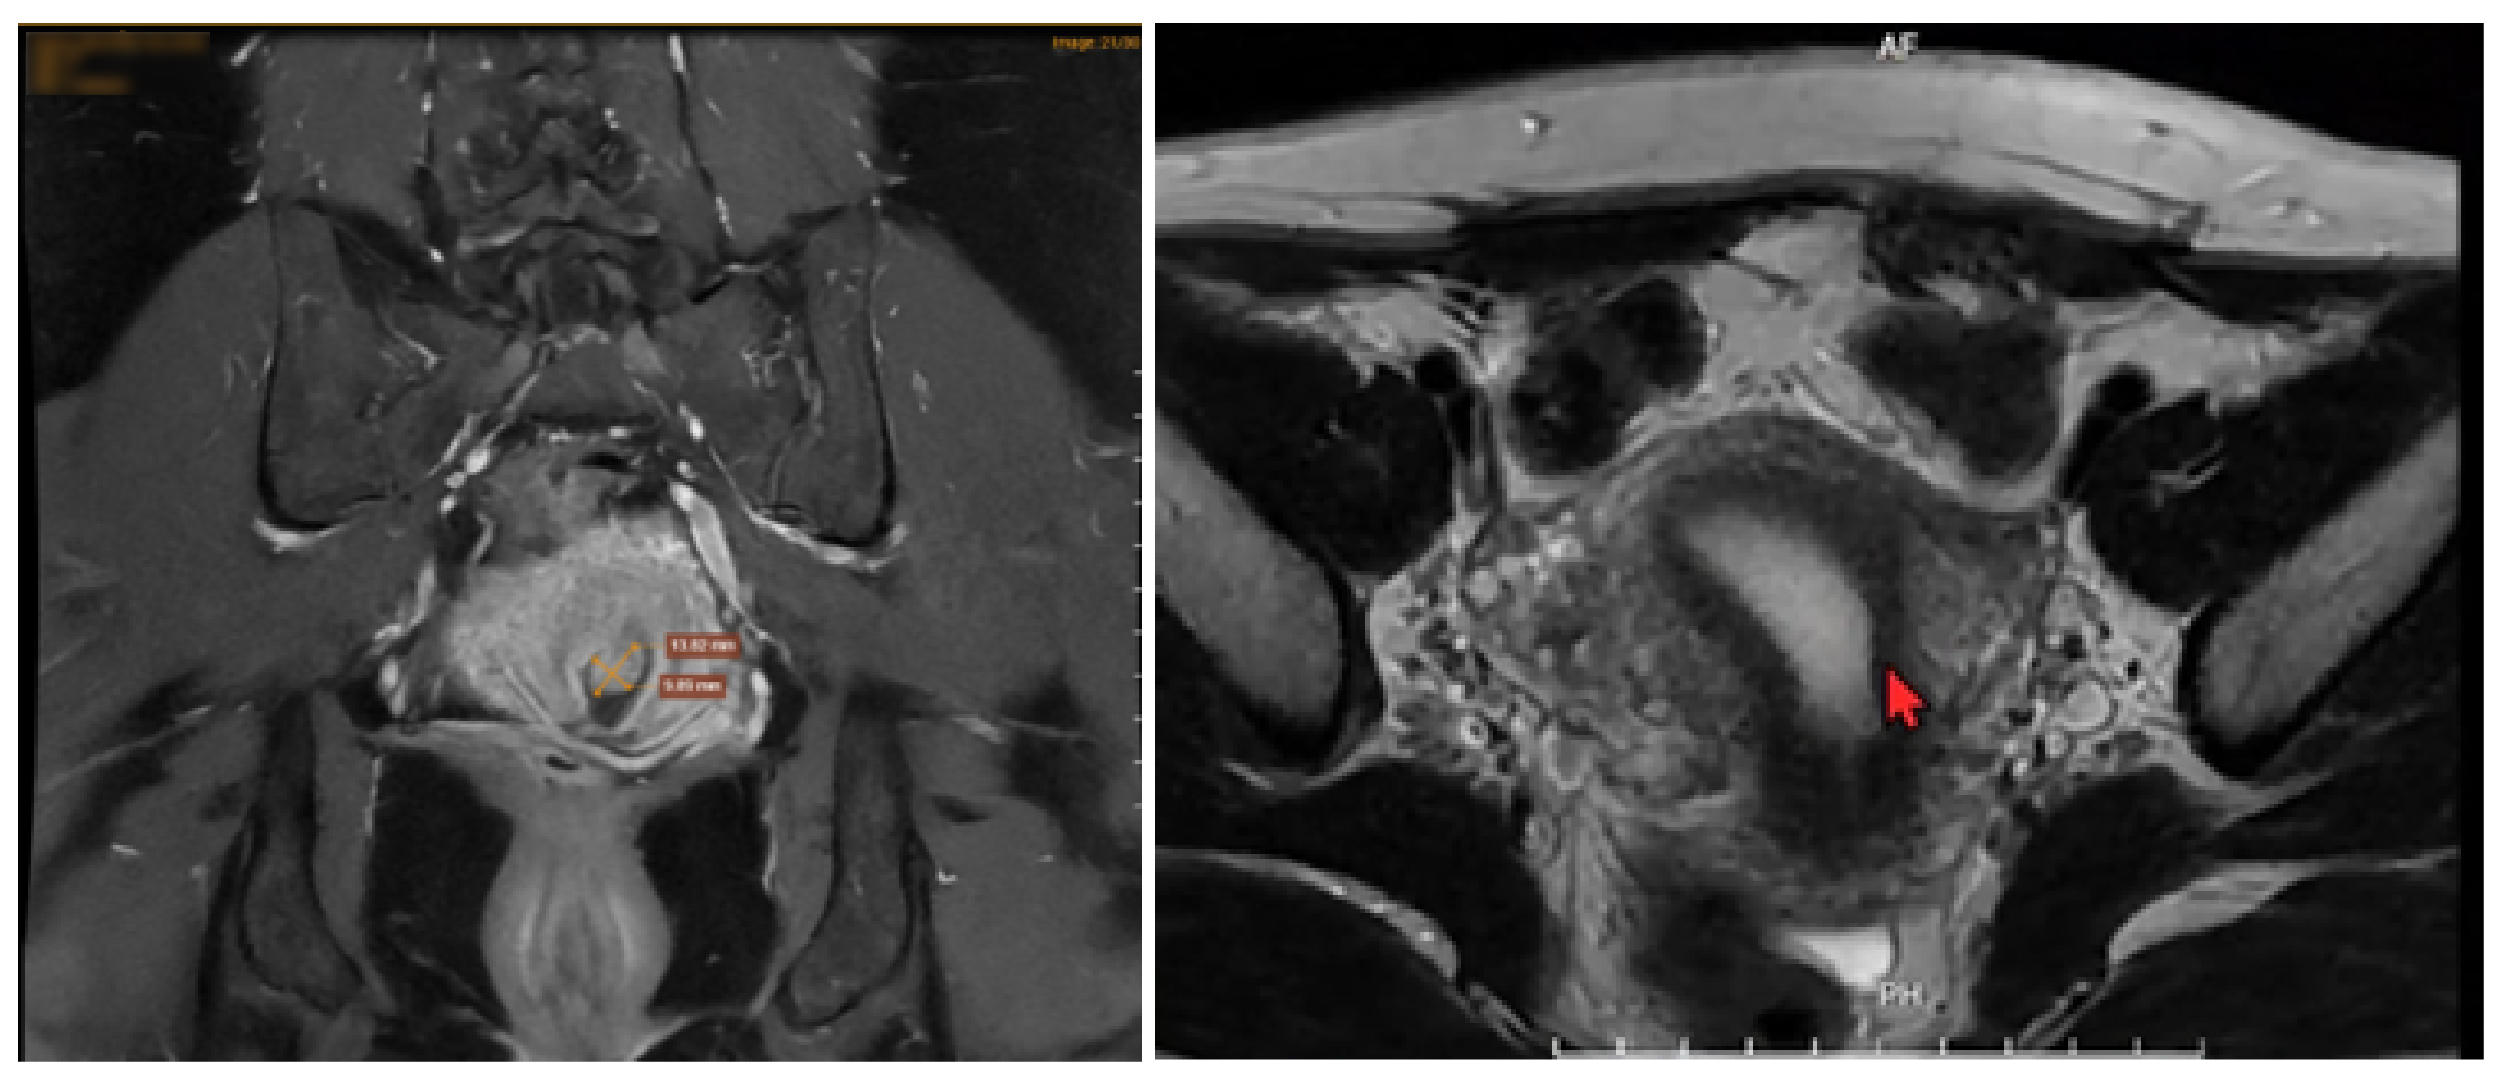

Kết quả đọc phim chụp MRI từ chuyên gia tại Trung tâm Chẩn đoán hình ảnh MEDLATEC cho biết, nguyên nhân gây ra cơn đau mạn tính của bệnh nhân là do khối lạc nội mạc tử cung thành bụng, đồng thời cần theo dõi polyp ống cổ tử cung, nhân xơ vú phải và viêm tuyến giáp Hashimoto.

Hình ảnh chụp MRI vùng chậu phát hiện cấu trúc tổn thương nằm trong cơ thành bụng vùng hạ vị bên trái. |